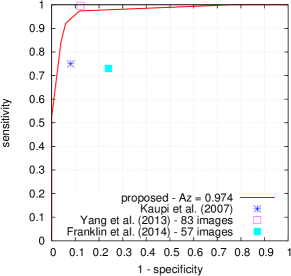

Given a target lesion type, Kauppi et al. (2007) proposed a standardized procedure to evaluate the performance of a lesion detector, at the image level, in the DiaretDB1 dataset. In this purpose, one probability map was constructed per image: this map was obtained by averaging, at the pixel level, confidences from all four experts for the target lesion type. If and only if this map contains at least one pixel with an average confidence level above 75 , then the image is considered to contain the target lesion. Based on this criterion, a receiver-operating characteristic (ROC) curve can be constructed for the lesion detector.

FROC curves are reported in Fig. 6 for ‘net B’; areas under the limited FROC curve for all three ConvNets are summarized in Table 3. It appears that the number of false alarms is rather large, particularly in the case of microaneurysm detection. The reason is that human experts primarily segmented the most obvious lesions, while screening algorithms need to focus on the most subtle lesions as well. In other words, many true lesions are counted as false alarms. Of course, this comment also applies to competing automatic solutions. To show the value of our detections, the proposed solution was compared in Fig. 7 to results reported in the literature, following the DiaretDB1 standardized procedure (see section 5.3.2). Most authors reported a single (sensitivity, specificity) pair: this is what we reported in Fig. 7. Some authors reported ROC curves; in that case, we also reported a single (sensitivity, specificity) pair: the one closest to the (sensitivity = 1, specificity = 1) coordinate. Note that all competing solutions (Kauppi et al., 2007; Yang et al., 2013; Franklin and Rajan, 2014; Kumar et al., 2014; Bharali et al., 2015; Mane et al., 2015; Dai et al., 2016) are trained at the lesion level, while ours is trained (in Kaggle-train) at the image level.

Three ConvNets were trained to detect referable DR in the Kaggle-train dataset, using the proposed heatmap optimization procedure. Then, we evaluated how well those ConvNets could detect lesions in the DiaretDB1 dataset, without retraining them. For lesion detection at the image level, they outperformed previous algorithms, which were explicitly trained to detect the target lesions, with pixel-level supervision (see Fig. 7). This superiority was observed for all lesions or groups of lesions, with the exception of ‘red lesions’. Experiments were also performed at the lesion level: for all lesion types, the proposed algorithm was found to outperform recent heatmap generation algorithms (see Table 3). As illustrated in two examples (see Fig. 9 and 10), the produced heatmaps are of very good quality. In particular, the false alarms detected on the vessels, in the vicinity of true lesions in the unoptimized heatmaps ( maps), are strongly reduced with sparsity maximization (, , ). These experiments validate the relevance of image-level supervision for lesion detectors, but stress the need to optimize the heatmaps, as proposed in this paper. Note that detection performance is not affected much by image quality: very good detections are produced in the blurry image obtained with a low-cost, handheld retinograph (see Fig. 10). This is a very important feature, which opens the way to automated mobile screening. However, it can be observed that the ‘AlexNet’ architecture, which achieves moderate DR detection results, also achieves poor detection results at the lesion level, even after heatmap optimization (see Table 3): to ensure good detection performance at the lesion level, the proposed optimization framework should be applied to ConvNet architectures that achieve good image-level performance.